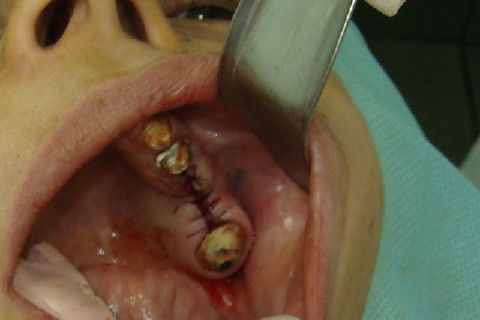

Abertura do retalho e inicio da remoção dos parafusos de osteossíntese na região 12

Abertura do retalho e inicio da remoção dos parafusos de osteossíntese na região 22